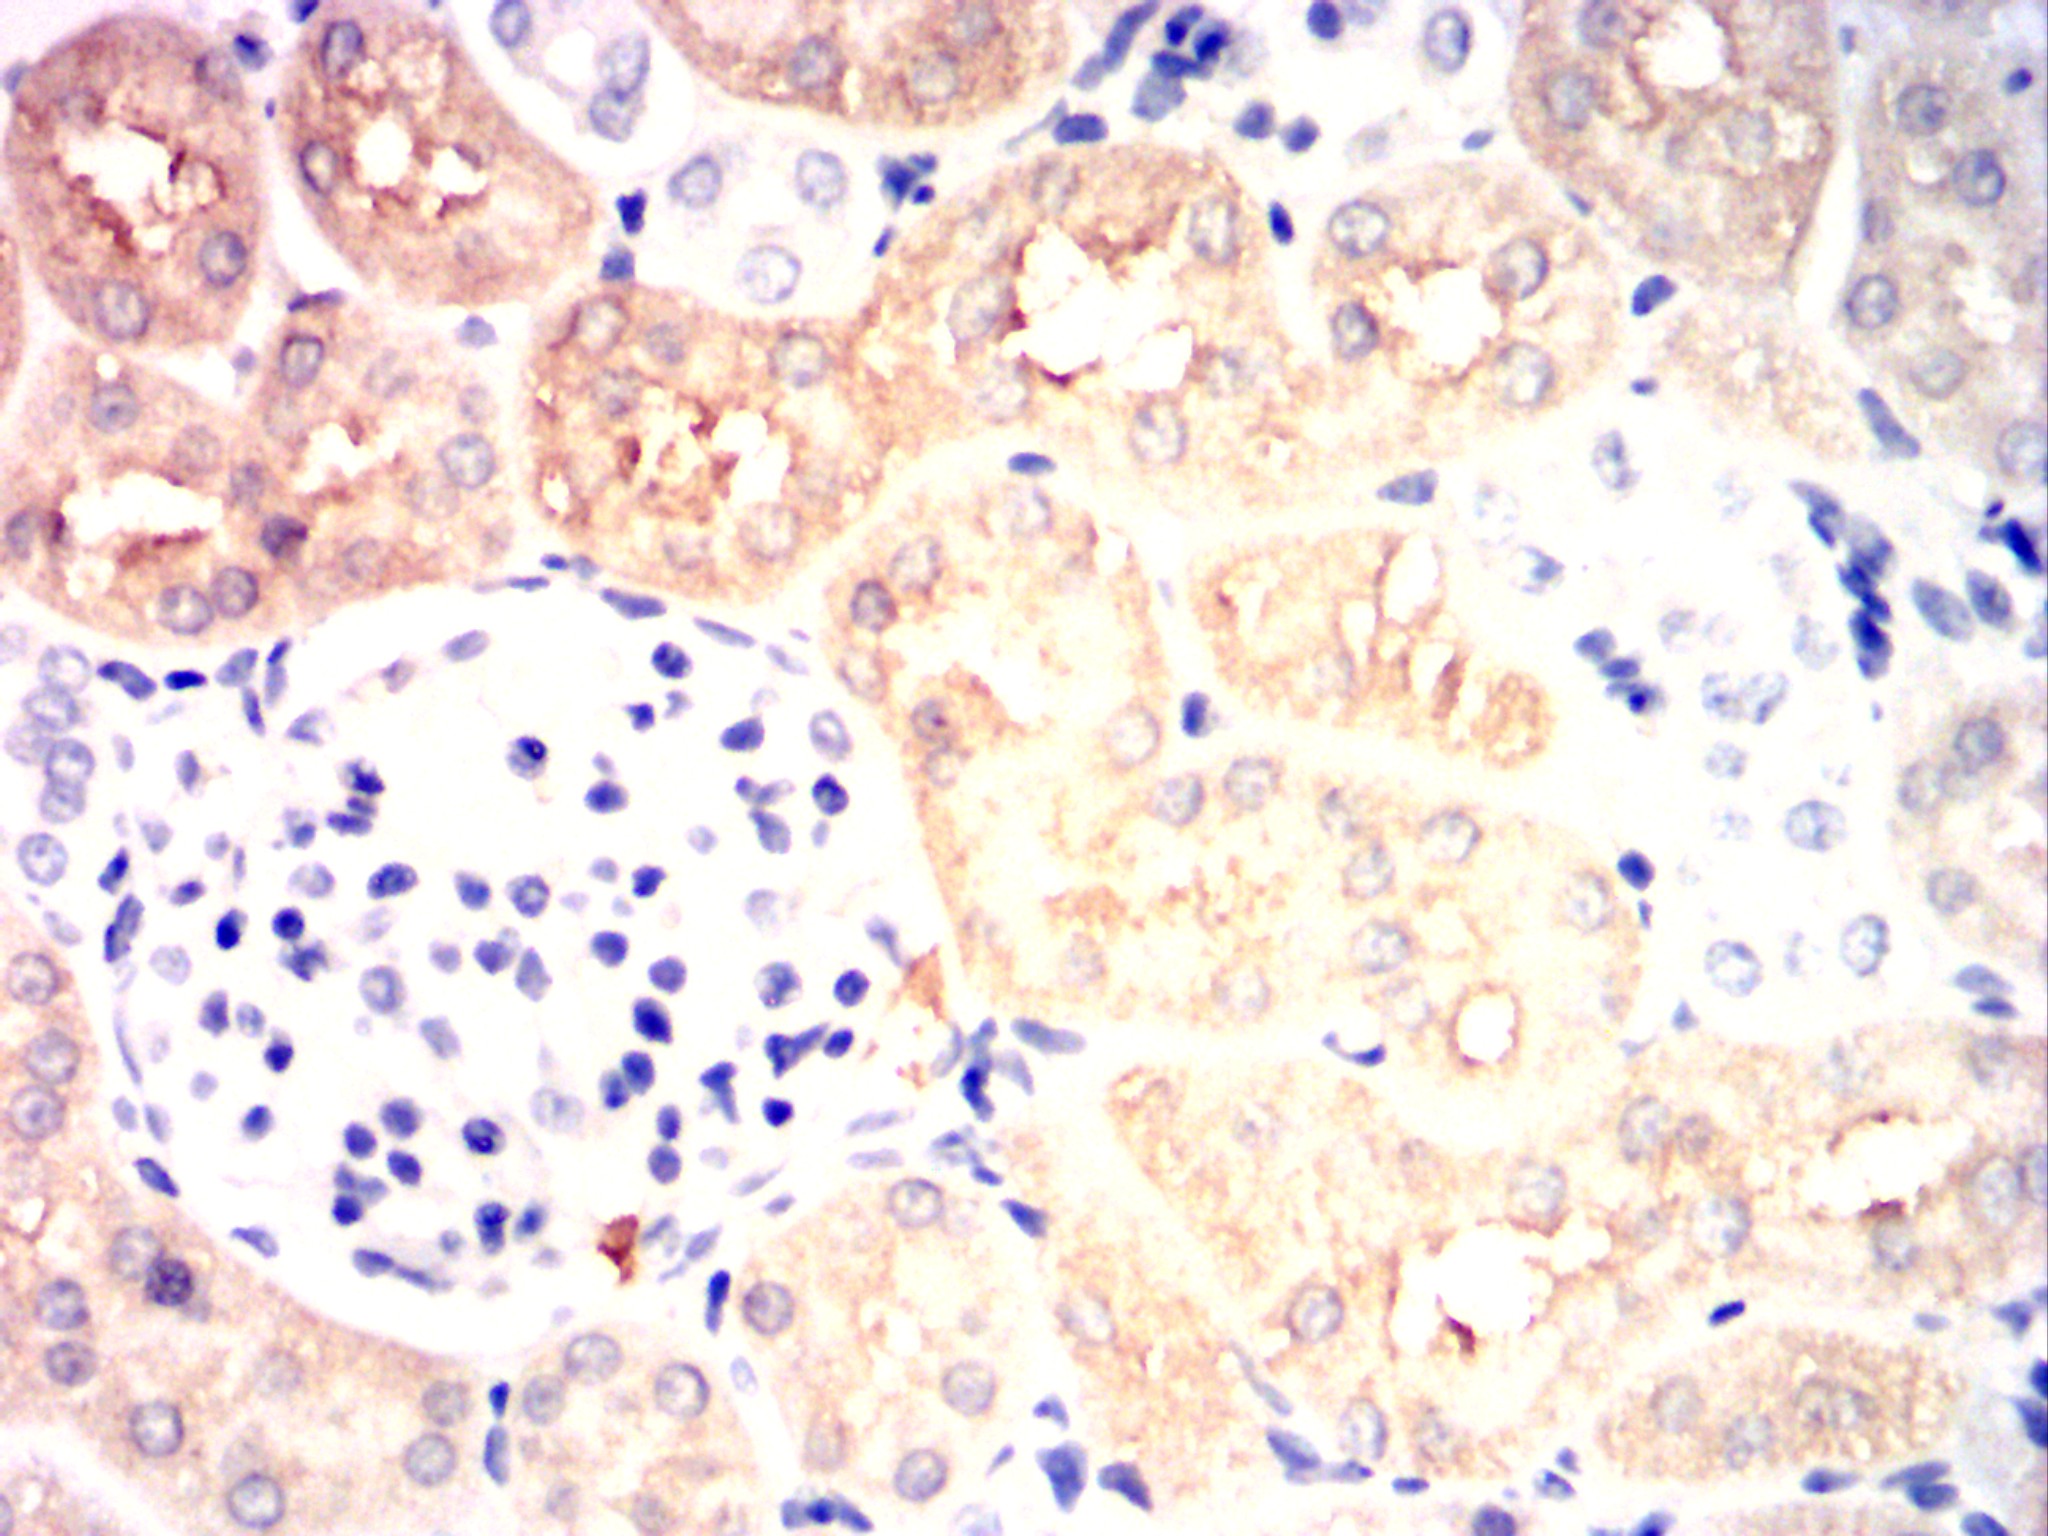

| IHC | 1/100 - 1/500 | Human,Mouse,Rat,Rabbit |

| Immunogen | Purified recombinant fragment of human HK2 expressed in E. Coli. |

The HK2 antibody targets hexokinase 2 (HK2), a key enzyme in glycolysis that catalyzes the first step of glucose metabolism by converting glucose to glucose-6-phosphate. HK2 is primarily localized to the outer mitochondrial membrane, where it couples glycolysis to mitochondrial ATP production, enhancing energy efficiency. Unlike other hexokinase isoforms (e.g., HK1), HK2 is highly expressed in metabolically active tissues and is frequently overexpressed in cancer cells. This overexpression supports the Warburg effect, a metabolic hallmark of cancer characterized by increased glycolysis even under aerobic conditions. HK2 also interacts with mitochondrial voltage-dependent anion channels (VDACs), promoting tumor cell survival by inhibiting apoptosis.

The HK2 antibody is widely used in research to study metabolic reprogramming in cancer, neurodegenerative diseases, and diabetes. It enables detection of HK2 expression levels via techniques like Western blot, immunohistochemistry, and immunofluorescence. Studies using HK2 antibodies have revealed its role in tumor progression, chemoresistance, and as a potential therapeutic target. Inhibitors targeting HK2-mitochondria interactions are under exploration to disrupt cancer metabolism. However, HK2's dual role in normal and pathological metabolism necessitates careful evaluation of therapeutic strategies. Overall, the HK2 antibody serves as a critical tool for understanding metabolic dysregulation and developing targeted therapies.